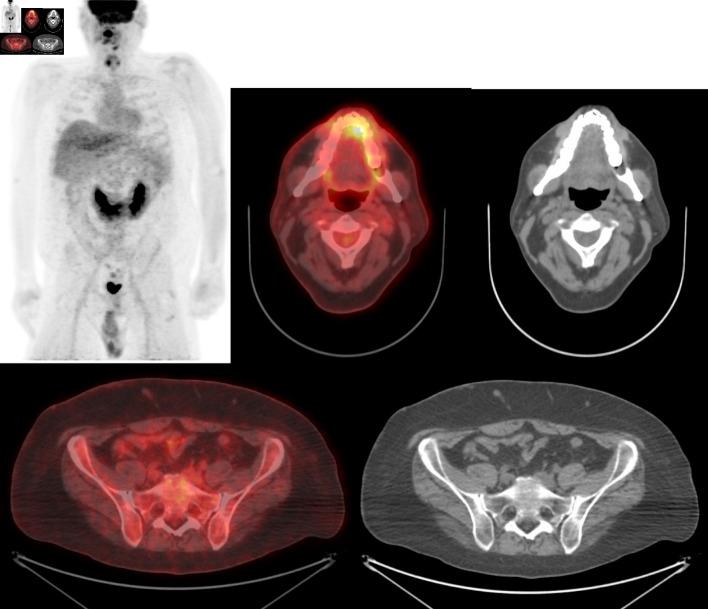

Induction multiagent chemotherapy can cure 70% of adult Burkitt lymphoma patients. However, for the remaining patients, the majority will relapse either during induction chemotherapy or within 6 months after initial complete remission, as in our patient. In this life-threatening presentation where no standard therapy exists with a response rate to salvage chemotherapy of 0% and a median survival of 6 weeks, there is an urgent need for novel, effective approaches to overcome chemoresistance in Burkitt lymphoma. Our report demonstrates that targeting B-cell receptor signaling via the phosphatidylinositol 3-kinase/protein kinase B (PI3K/AKT) pathway with copanlisib can overcome chemotherapy resistance and achieve complete remission in relapsed Burkitt lymphoma. This novel approach, followed by consolidation with allogeneic hematopoietic stem cell transplantation can provide durable complete remission by harnessing the immune graft-versus-lymphoma effect in chemoresistant Burkitt lymphoma.

诱导多药化疗可治愈70%的成年伯基特淋巴瘤患者。然而,对于其余患者,大多数会在诱导化疗期间或首次完全缓解后的6个月内复发,就像我们的患者一样。在这种危及生命的情况下,没有标准治疗方法,挽救性化疗的缓解率为0%,中位生存期为6周,迫切需要新的有效方法来克服伯基特淋巴瘤的化疗耐药性。我们的报告表明,使用库潘尼西通过磷脂酰肌醇3激酶/蛋白激酶B(PI3K/AKT)途径靶向B细胞受体信号传导,可以克服化疗耐药性,并使复发的伯基特淋巴瘤实现完全缓解。这种新方法,继之以异基因造血干细胞移植巩固治疗,可以通过利用免疫移植物抗淋巴瘤效应,在化疗耐药的伯基特淋巴瘤中实现持久的完全缓解。